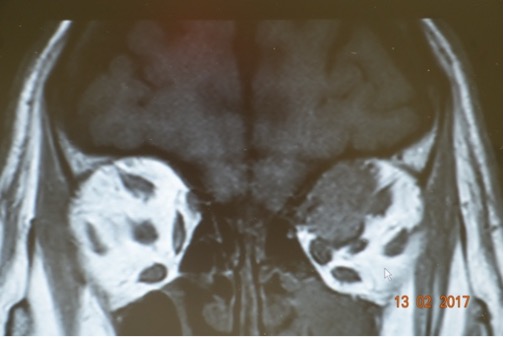

- Resonancia Magnética

Las nuevas tecnologías permiten obtener imágenes muy precisas que nos ayudan en el diagnóstico del tumor y nos guían durante la cirugía.